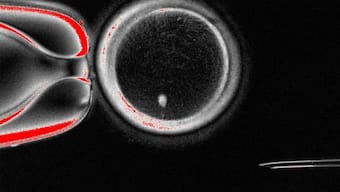

An image of an oocyte with a bright image of a skin cell nucleus before fertilisation.  Image courtesy: Oregon Health & Science University